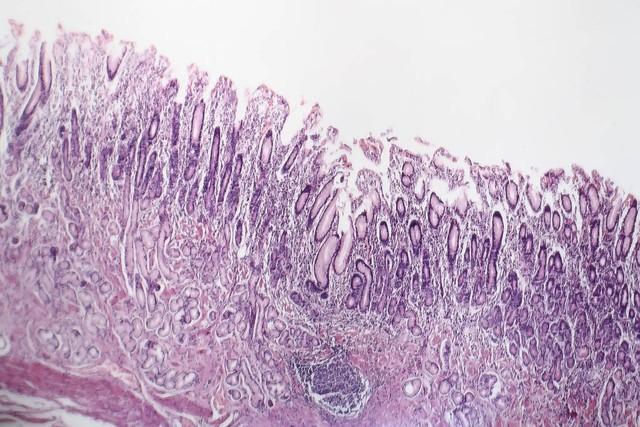

诊断慢性非萎缩性胃炎主要依靠胃镜检查和病理活检。胃镜下,慢性非萎缩性胃炎可能表现为黏膜充血、水肿、红斑、粗糙糜烂或渗出等改变。然而,仅凭内镜表现有时难以准确判断是否为萎缩性胃炎,因此病理检查至关重要。2014年的一项研究显示,以病理诊断为“金标准”,内镜诊断萎缩的敏感度仅为42%,特异度为91%。这意味着,即使内镜下未见明显异常,也不能完全排除萎缩性胃炎的可能性。